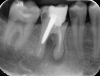

Fig 2. Improper metal post placement/perforation (dentistry courtesy of Riccardo Tonini, MD, DDS).

Figure 2

Furthermore, the reconstruction of endodontically treated teeth can present restorative and esthetic challenges for the technician and clinician.23 The failure of these post-retained systems has been documented in numerous clinical studies.10,13,21,24-29 Many of these studies indicate that the failure rate of restorations on pulpless teeth with posts and cores is higher than that for restorations of vital teeth because of their structural differences and the significant loss of tissue.30-35 Several main causes of failure of post-retained restorations have been identified, including recurrent caries, endodontic failure, periodontal disease, post dislodgment, cement failure, post-core separation, crown-core separation, loss of post retention, core fracture, loss of crown retention, post distortion, post fracture, tooth fracture, root perforation (Figure 1), improper post placement (Figure 2), and root fracture.11,36,37Also, corrosion of metal posts has been proposed as a cause of root fracture.38 A post and core system fabricated with dissimilar metals can cause galvanic corrosion that occurs between the two dissimilar materials.39 This gradual destructive process involves the electrical interaction of at least two different metals or nonmetallic conductors in an environment (ie, microleakage) that accelerates the corrosion of at least one of them, while the least noble metal corrodes the most.